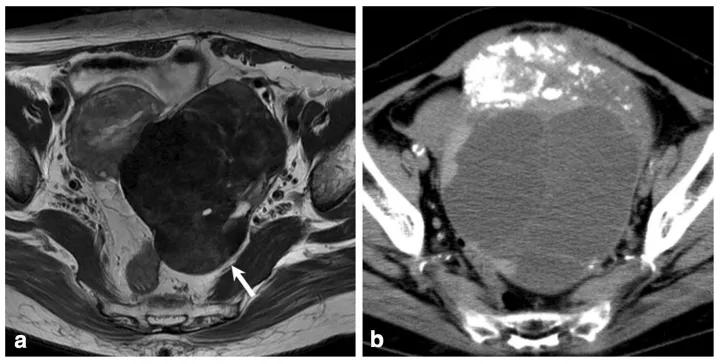

图 1. 女,22 岁,左侧卵巢硬化性间质瘤。CT 示左侧附件区囊实性巨大肿块,增强后肿瘤周边呈明显持续性强化,肿块周边多发结节及乳头状强化,中央囊性成分未见明显强化。

图 2. 女,42 岁,左侧卵巢硬化性间质瘤。盆腔内巨大囊实性肿块,平扫呈等密度,肿块内部及周边多发絮状及乳头状结节,增强后肿块呈持续性显著强化,向 心性推进,强化绒毛呈「梳齿样」强化。

图 3. 女,19 岁,左侧卵巢硬化性间质瘤。T2WI 轴位(图 3B)示盆腔内囊实性肿块,实性区域与囊变区相交错,呈「梳齿样」表现,肿块边缘见低信号包膜,实性成分呈结节及乳头状等信号,中央囊变区呈裂隙状稍高信号,低信号包膜下见流空血管影(箭头),增强扫描轴位(图 3CD)静脉期及延迟期盆腔内肿块周围实性成分呈显著持续性、向心性强化;中间裂隙状囊变区无强化,表现为「湖岛」征。